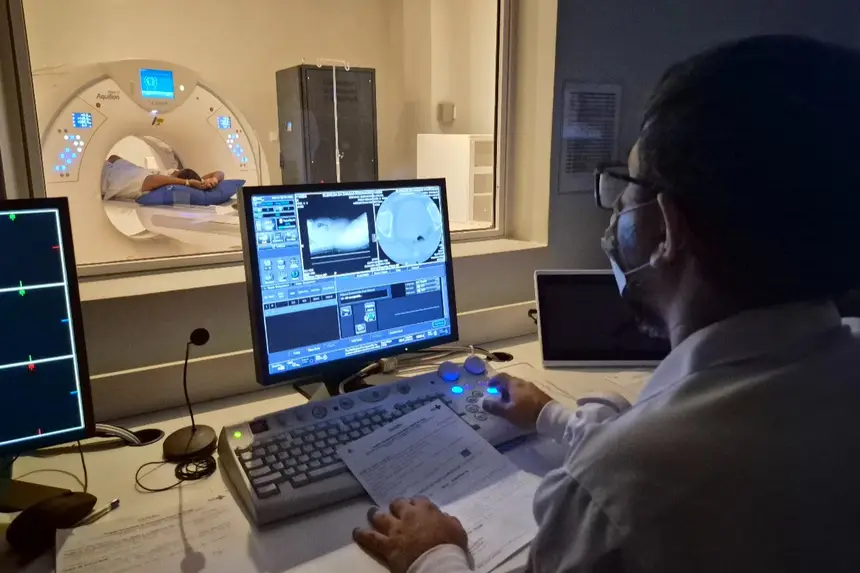

“Essa inauguração representa um grande passo no que diz respeito à rede do Hospital Universitário e à assistência no estado do Amapá, contribuindo para desafogar o Sistema Único de Saúde (SUS), que registra uma alta demanda por esses serviços, cujo agendamento é feito por meio da rede Super Fácil do Governo do Estado”, destacou o superintendente do HU no Amapá, o médico Marcos Santos.

Segundo ele, há uma alta incidência de pacientes com problemas neurovasculares no estado, e o hospital chega para agilizar o atendimento no SUS, ampliando a oferta de assistência especializada.

A usuária do SUS Emilly Nicoly Costa Soares foi uma das primeiras a utilizar o novo equipamento de tomografia.

“Foi muito bom estrear o equipamento, porque eu estava esperando há muito tempo. Meu marido está me acompanhando e sabe o quanto foi difícil conseguir. Agora deu tudo certo, graças a Deus. Foi um sucesso. O ambiente é frio, mas faz parte”, relatou a paciente.

O Centro Tecnológico é composto por aparelhos de ressonância magnética, tomógrafo computadorizado, equipamento de mamografia, raio X telecomandado e densitometria óssea.

Os equipamentos foram adquiridos por meio de contratação e fazem parte do plano de qualificação de exames por imagem.